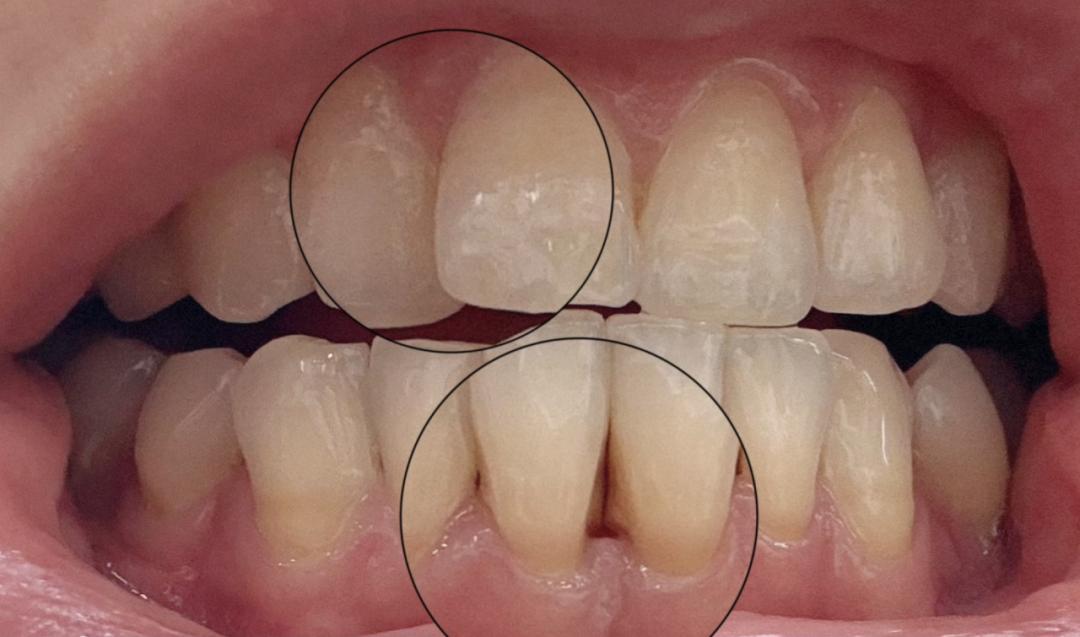

② 鈣化變硬:沒被及時清理掉的牙菌斑,會混合唾液鈣化,變成牙結石,像水泥一樣擠壓刺激你的牙齦,導致出血、發炎,口臭,甚至是牙!齦!萎!縮!掉!